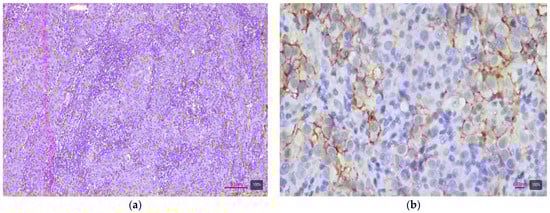

2.4. Immunohistochemical Study of HER2

2.5. Interpretation of HER2 Status